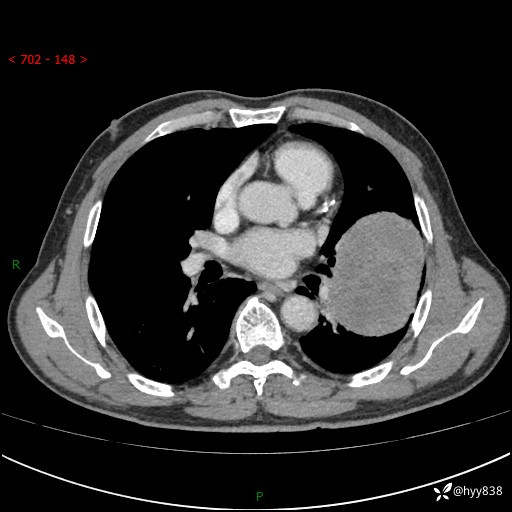

68岁/男,发现左下肺占位5天。如此大的肿块,患者竟然没有症状---结果公布~

【患者信息】:68岁/男

【主诉】:检查发现左下肺占位5天。

【现病史及既往史】:患者于4天前外院行“经尿道钬激光碎石术”,住院期间胸部CT检查发现左下肺肿块,患者平素无明显咳嗽咳痰,无心慌、胸闷、胸痛、呼吸困难、低热、盗汗,无头痛、头晕,无腹痛、腹胀等不适,现患者为求进一步治疗,遂来我院就诊,以“左下肺肿块”收入我科。 患者自起病以来,精神可,睡眠可,饮食可,大小便正常,体重无明显改变。

【检查】:胸部CT增强扫描